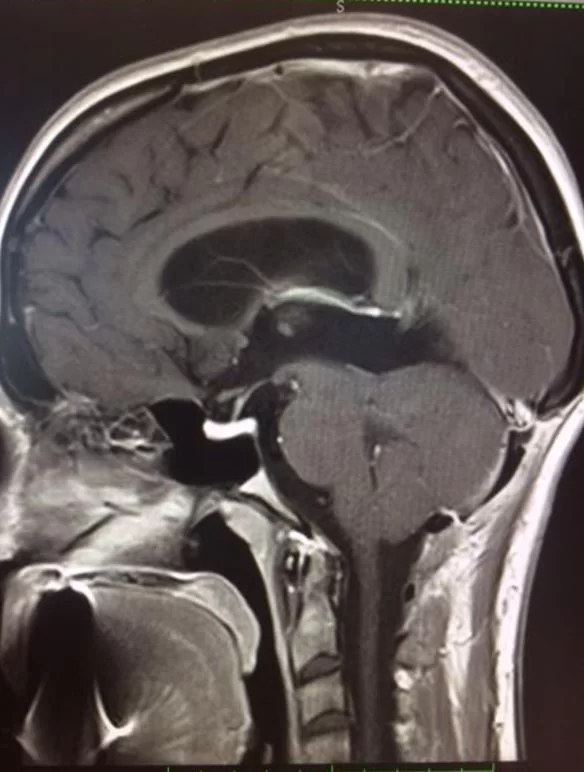

Η μετεγχειρητική αξονική τομογραφία εγκεφάλου δείχνει πλήρη αφαίρεση της βλάβης. Η ιστολογική εξέταση ανέδειξε πινεαλοκύττωμα (WHO I).